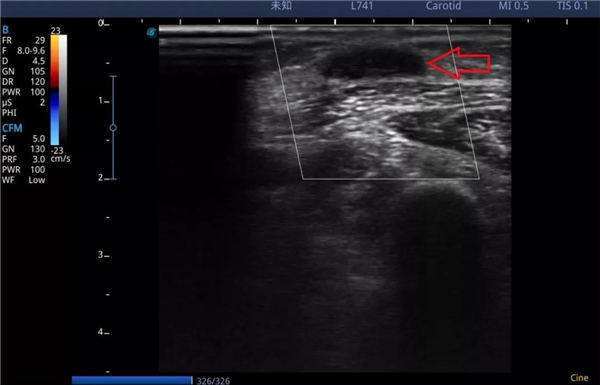

谭老先生和老伴赶到燕化医院一检查,果不其然是桡动脉贵要静脉内瘘闭塞了。如图,超声下闭塞的贵要静脉,完全没有彩色血流。